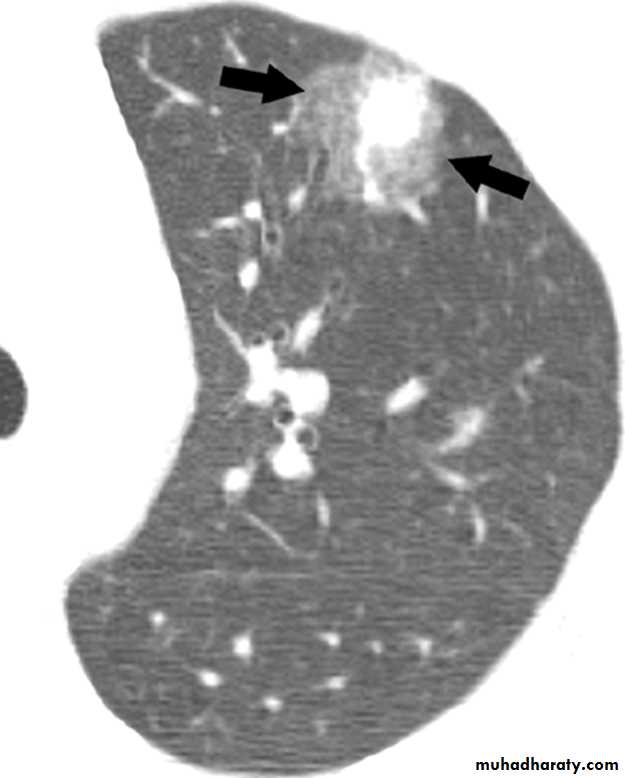

You arrange for CXR which show no much abnormality. CT chest done and shown.

Neutrophil count is 2 x 109/L

Multiple iv antibiotics given for 4 days with no response.What is the most likely Dx?